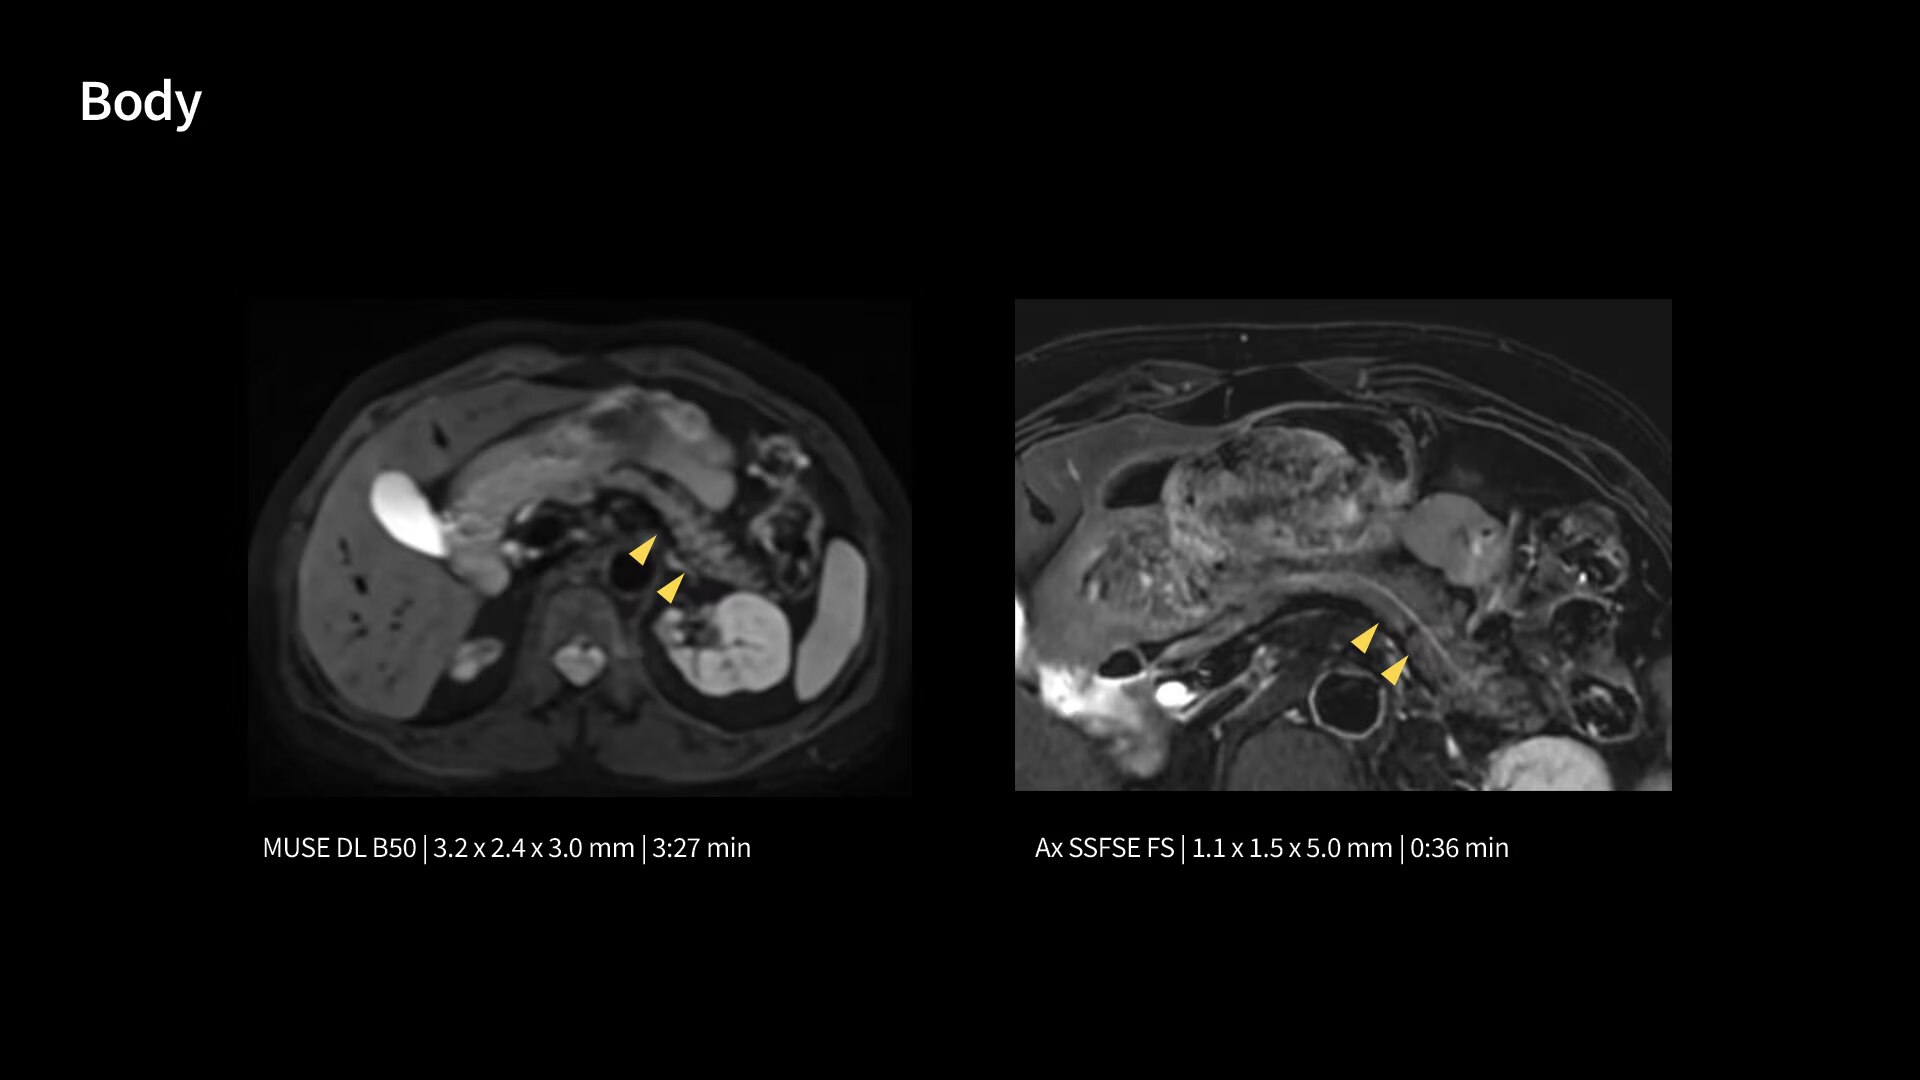

In oncological assessments, diffusion imaging is a critical clinical indicator. SIGNA Sprint offers clearer diffusion, reduced distortion and improved SNR.¹

The growing clinical need within oncology and cardiology requires an MRI scanner that can rise to the challenge. With a high gradient performance of 65/200, SIGNA Sprint helps deliver crystal-clear imaging for ultimate diagnostic confidence. Improved signal-to-noise ratio (SNR) and diffusion, with deep-learning solutions that could enhance diagnostics and treatment response monitoring in your oncology patients.¹ Additionally, the shift from qualitative to quantitative cardiac MRI reduces the time and expertise needed to interpret scans and offers greater consistency and reliability. Helping you to unlock the power to explore further - even in your most challenging cases.